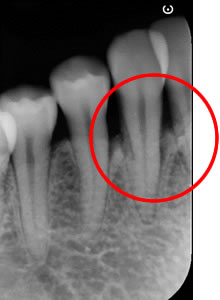

■治療後のエックス線写真

歯の周りには、歯周組織、骨が再生され歯周ポケットは3mmになりました。